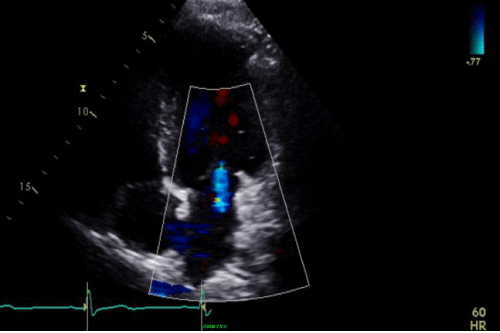

c) Repeat Echocardiogram: Normal RV size and function with trivial TR (Figure 8).

Cine 4: SR with VR = 66 bpm

TTE apical 4-chamber view demonstrating trace TR with color flow